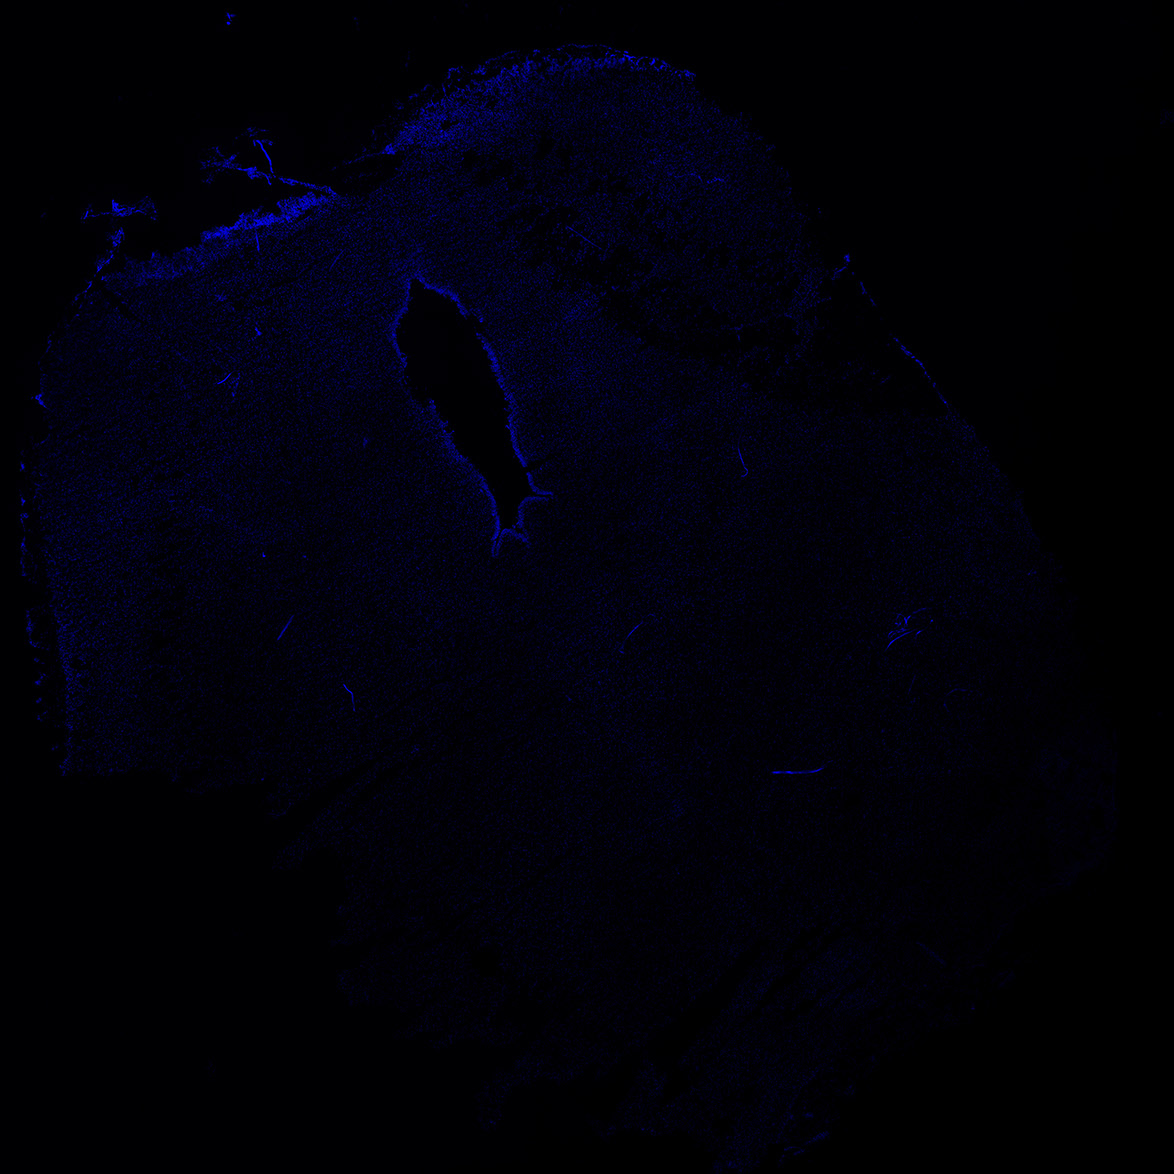

An anatomical analysis of the developing human midbrain from 6 post-conceptional weeks (PCW) to 22 PCW reveals increased tissue complexity, characterized by the emergence of dopaminergic nuclei, as highlighted by immunofluorescence analysis for tyrosine hydroxylase (TH).

DAPI

22PCW human midbrain

GFAP

TH